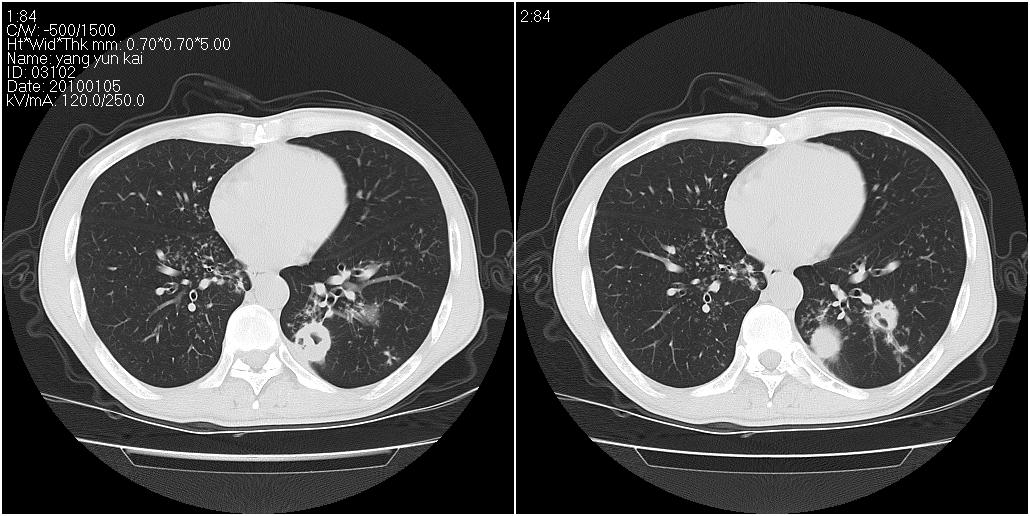

男性,47岁。近来咳痰、咳血,血沉增快(40左右),痰中未检出结核杆菌。

两肺继发性肺结核并多发性结核球形成,部分病灶内空洞形成。